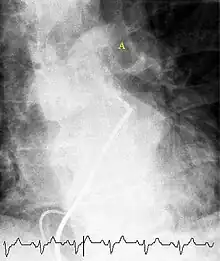

(A) After inhalation of 20 mCi of Xenon-133 gas, scintigraphic images were obtained in the posterior projection, showing uniform ventilation to lungs.

(B) After intravenous injection of 4 mCi of Technetium-99m-labeled albumin, scintigraphic images shown here in the posterior projection. This and other views showed decreased activity in multiple regions.

A ventilation/perfusion scan (or V/Q scan or lung scintigraphy) shows that some areas of the lung are being ventilated but not perfused with blood (due to obstruction by a clot).[19] This type of examination is as accurate as multislice CT, but is less used, due to the greater availability of CT technology. It is particularly useful in people who have an allergy to iodinated contrast, impaired kidney function, or are pregnant (due to its lower radiation exposure as compared to CT).[64][65][66] The test can be performed with planar two-dimensional imaging, or single photon emission computed tomography (SPECT) which enables three-dimensional imaging.[57] Hybrid devices combining SPECT and CT (SPECT/CT) further enable anatomic characterization of any abnormality.[67]